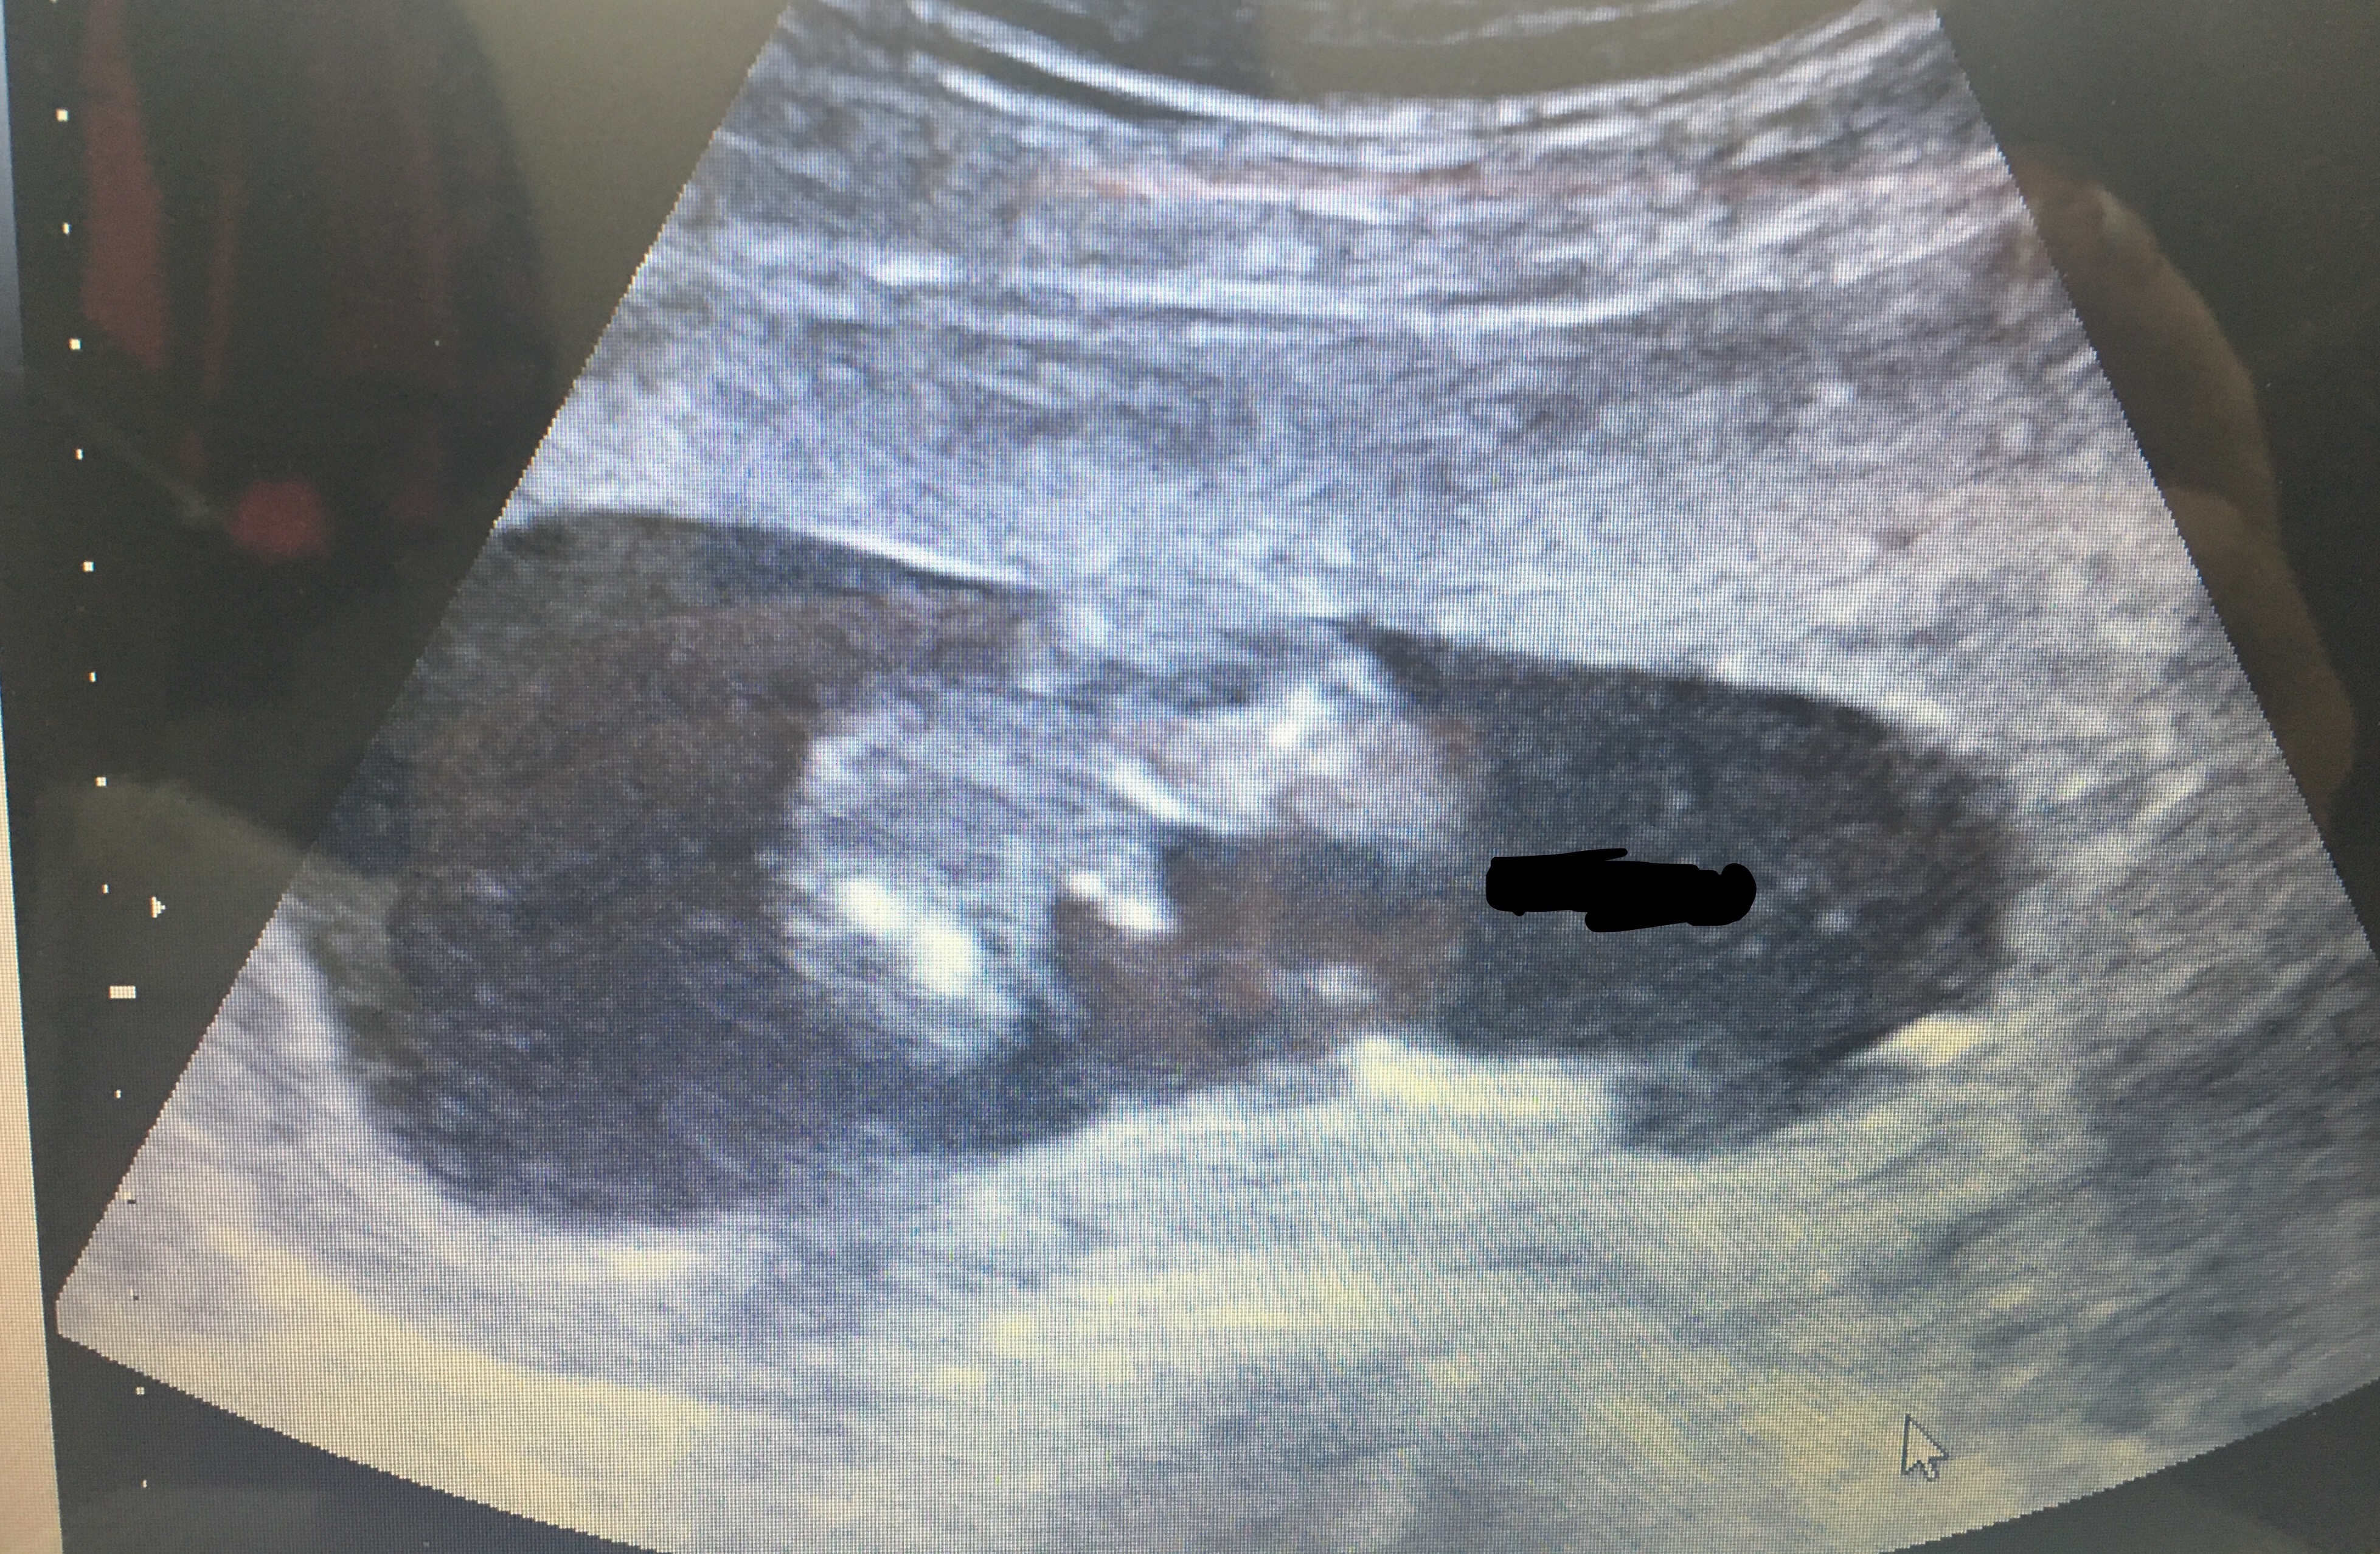

12 wks 5 days